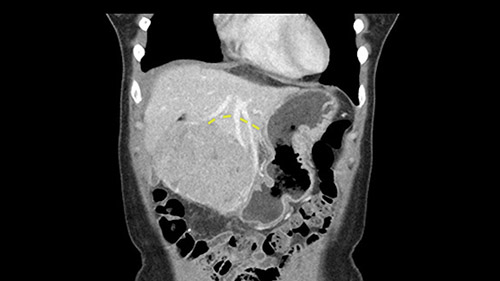

So if we look at the CT scan, on the axial, it’s a larger lesion. It’s about 6 or 7 or 8 centimeters. So it does look a bit threatening in terms of its resectability but if you really drill down deeply into the anatomy, and I think the coronal [imaging] is even better, you can see that the entire mass is on the patient’s left side of the falciform ligament. So it’s really only a left-sided tumor and not even really a left-sided tumor because Segment 4 is uninvolved anatomically.

None of the parenchyma is affected and this tumor is very exophytic; like many Hepatitis B hepatomas; and otherwise is resectable with either a wedge resection part of Segment 2-3 or a formal left lateral segmentectomy.

Some of my colleagues thought it may be involving Segment 4 and we’d need a formal left hepatic lobectomy, dividing anatomically: the left portal vein, left hepatic artery, left bile duct. But I didn’t think so, but you can see there is a challenge in terms of being certain where this tumor is located. So we’re prepared to do any of those 3 but my person view is that its going to be an exophytic tumor off of the left lateral segment and probably a wedge.

As I review the CT scan, we have both arterial and venous phases, the tumor is obvious. But I’ll start by saying that the liver itself does not appear to be cirrhotic to my eye. It’s got a normal contour and allied to that, that I do not see evidence of portal hypertension. The spleen is normal, there’s no collateral vessels. The tumor itself, I measured maximally at about 11 centimetres in diameter and I’m told the alpha fetoprotein is very high (over 10000), which is entirely consistent with this being a solitary hepatocellular carcinoma that is very exophytic. It seems to emanate off the inferior margin of Segment 3 (because that’s the falciform). I’ll start by saying that this is not transplantable. The tumor exceeds our guidelines for transplantation, but it's likely resectable based on normal liver and no portal hypertension.

So the issue with regards to resection. A left sided tumor. I believe I can see the falciform ligament right here so we’re looking at a resection of Segments 2, 3 of the left lobe of the liver. The left portal vein is right there. I think we’ll be wiser to take the left portal vein and therefore get well into Segment 4 and do a left hemihepatectomy. Certainly, one does not need to take the middle hepatic vein; it’s miles from the tumor.

We note that the tumor is pushing on the gallbladder but I think that’s probably external for the most part. I think that’s extrahepatic. I believe that Segment 4b is probably free of tumor. I’d have to say that it's tempting, particularly looking at the coronals, to consider a very limited resection. Where you’d just chip it off the bottom of Segment 3 and do a limited Segment 3 resection. I’d be concerned about the oncologic margins. I believe that the best oncologic operation will be to take the left portal vein to get this. Certainly, she’s got plenty of liver and she’d be able to sacrifice Segments 2-3 of the left lobe of the liver. It’s not necessary to take too much of thus of Segment 4a. But once one takes the portal vein, that will be compromised. So I would do a left hemihepatectomy on this woman.

Hi my name is Sedat Karademir. I’m from Ankara Guven Hospital and I’m an HPB and transplant surgeon. We are discussing about the case I reviewed the CT of 41 year old lady with a suspected hepatoma in the left lateral segment. Presumably its Segment 3. It looks like a big tumor sitting exophytically mostly out of the liver and pressing on the surrounding organs, but it doesn’t look like any invasion there. In this situation, according to the venous and arterial anatomy, it looks like this will be a Segment 2 and 3 resection.

The tumor is so close to the falciform ligament, I had a question mark about the Segment 4b relation between segment 4b and segment 3. In a normal resection of segment 2 and 3, we would be keeping on the left side of the falciform ligament and start getting segment 3 and 2 portal pedicles but in here its getting so close. So oncologically, 4b should be checked during the OR.

So in planning for this operation, as I look at the scans, I first visualize the arterial phase and I can see that there’s are a lot of big feeding arteries to this large tumor. Likely all the right side vessels feeding the right side of the liver: right hepatic artery and likely the Segment 4 artery are spared from the tumor. It’s likely the left hepatic artery is ramificating and giving feeding arteries to this tumor. It certainly looks like a large mass that its compressing other structures like the cava, the pancreas, the stomach; but I think there’s a plane and we can see that better in the venous phase. There’s a plane of separation between the gallbladder, the pancreas, the cava, that this tumor is abrupting but likely not invading. Usually, these masses actually don’t invade at that level and basically are pushing the tissues and once you open, you’re able to separate the tumor. Sometimes there’s some adhesions but you can actually separate and there’s usually no invasion.

The other thing I would do in this case is to certainly to assess the coronal phase as we can see in the coronal phase, this tumor looks like it's growing from Segment 3, and again I don’t think there’s involvement of the right side of the liver or even on Segment 4.

So in terms of planning on the surgery, I think there’s two clear options for this patient and that we’ll need to assess once we’re in the operating room. One option would be to do a Segment 3 resection. This tumor seems like it's hanging from Segment 3 so I think if we can get a good margin, that would be an option. Of course the other option is to do a left hepatectomy, preserving the middle hepatic vein, which is clearly not involved with the tumor.